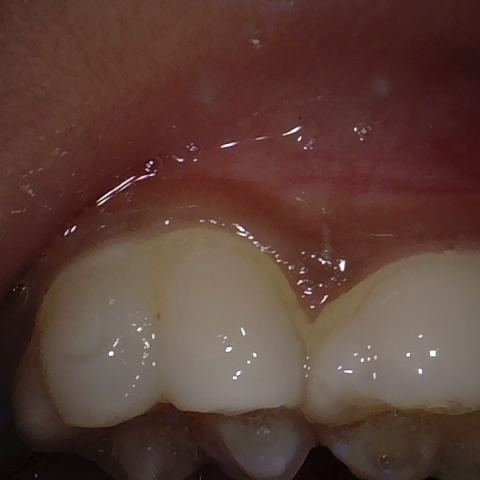

Annotated as "Good"